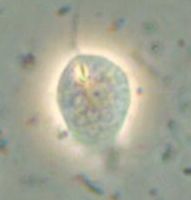

七面鳥、ウズラ、クジャク、ヤマドリに自然感染がみられますが、特に七面鳥に重要で、1~9週齢の雛鳥が最も感受性が高い。

寄生部位は十二指から空腸上部であり、急性カタール性腸炎を生じます。感染鳥の上部小腸はカタール性腸炎により腸壁は嚢状に薄くなり、腸管内には泡沫を含む水様性の滲出液がみられます。